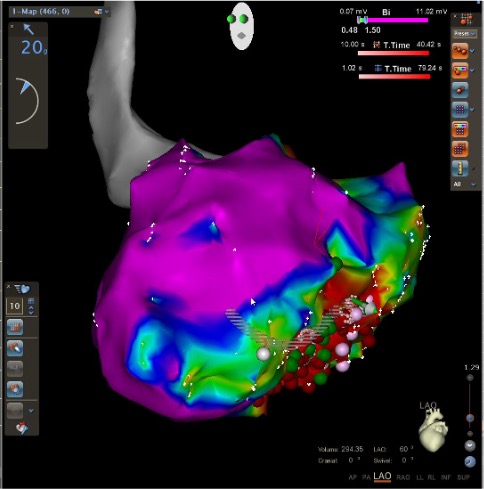

Treatment depends on the severity of VT, symptoms, and underlying heart disease. Common treatments include:

Targets and eliminates abnormal electrical pathways